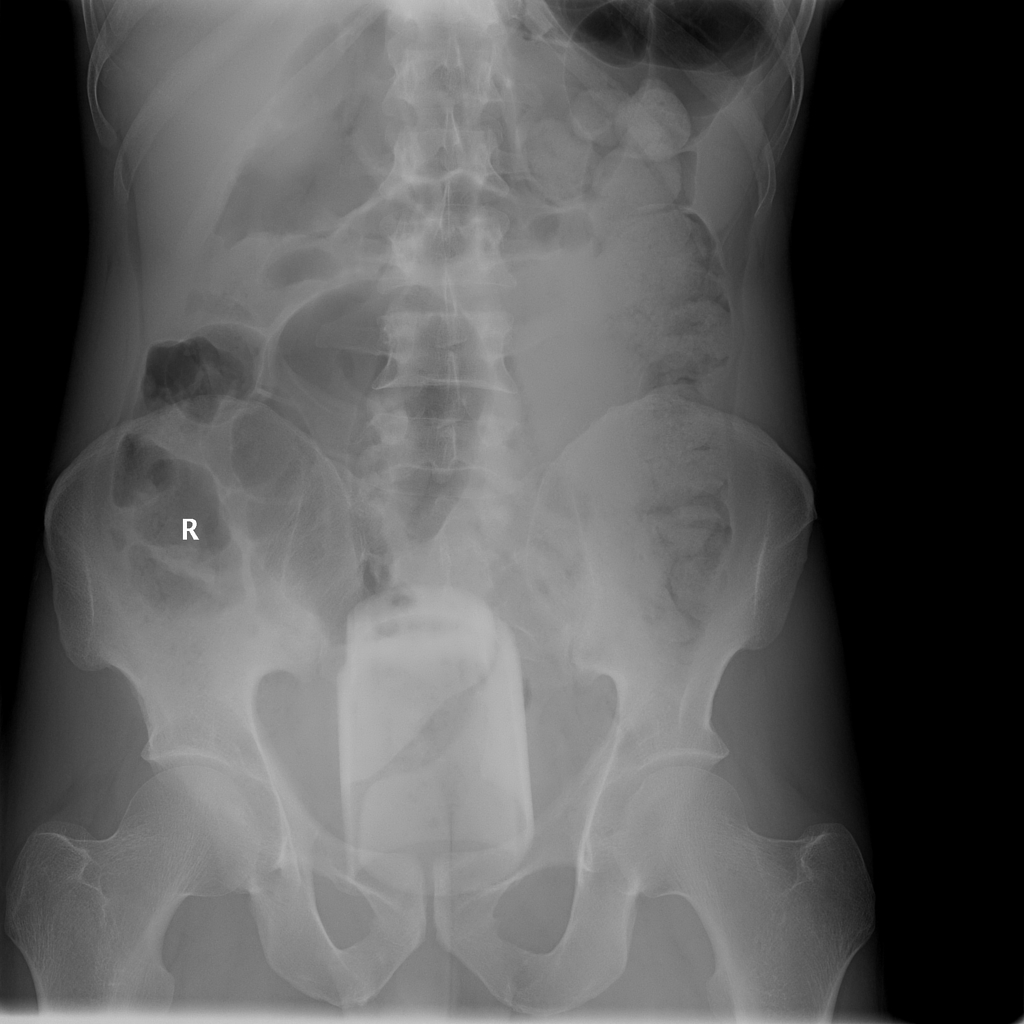

Необычные находки: инородные тела на рентгенограмме брюшной полости